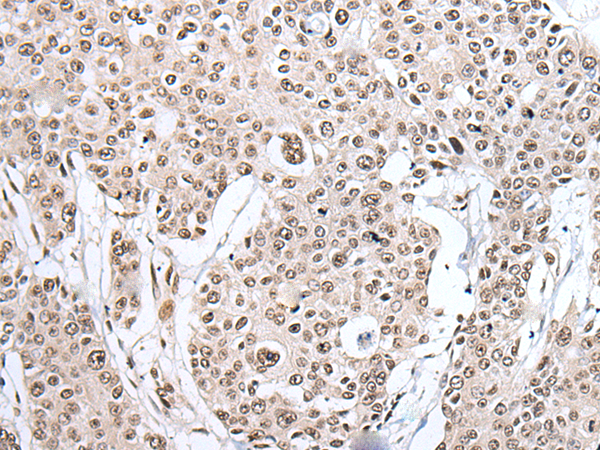

IHC positive control:

Human esophagus cancer and human liver cancer

IHC Recommend dilution:

25-100